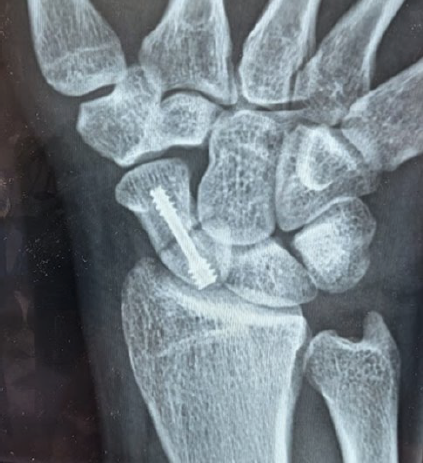

手術療法: 最近では、ズレが小さくても早期に社会復帰やスポーツ復帰をするために、小さなネジ(スクリュー)で骨を固定する手術(右写真)が選択されることも多いです。ズレがある場合は手術が推奨されます。骨癒合が得られずに偽関節になってしまった場合は、自分の他の部位から骨を移植する手術が必要になることもあります。